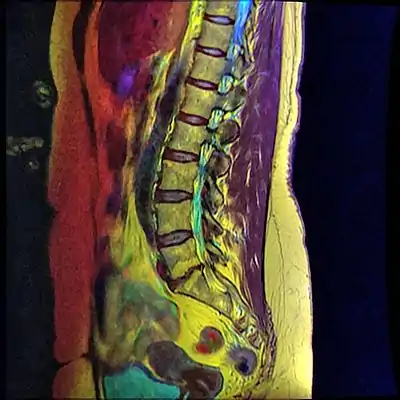

![]() | |